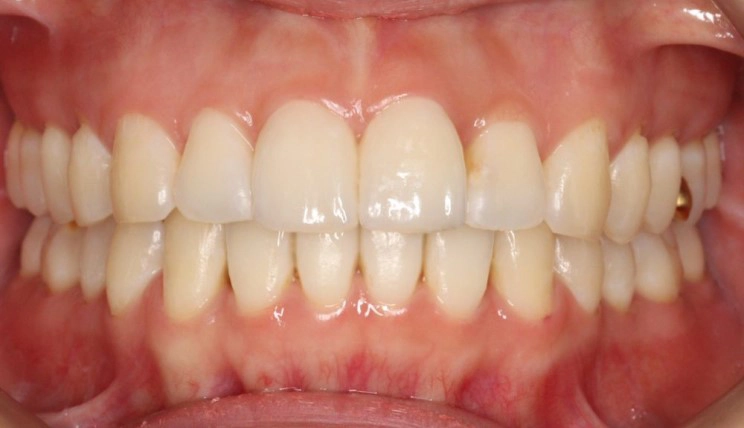

Deep Bite

Deep bite is the condition in which the vertical overlap of anterior teeth in centric occlusion is larger than 30 – 40%.

Patient Information:

Age: 13

Gender: Male

Invisalign Treatment Option: Invisalign Comprehensive

Total Treatment Time:

24 months